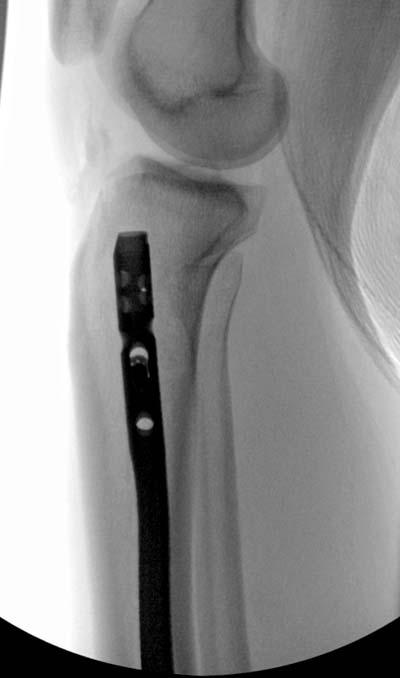

Здесь несколько снимков изолированного перелома большеберцовой с интактной малоберцовой. Weber clamp, блокирующие спицы и риминг в центре канала отрепонировал перелом....

В нашем распоряжении были все размеры гвоздей, но взяли этот.

Следующий размер на 15 мм больше и доходил до уровня сустава. Иногда даже самая идеальная фиксация не гарантирует сращение, надо оставить запас для динамизации. Дистально исчерпан лимит, а проксимально достаточно места...